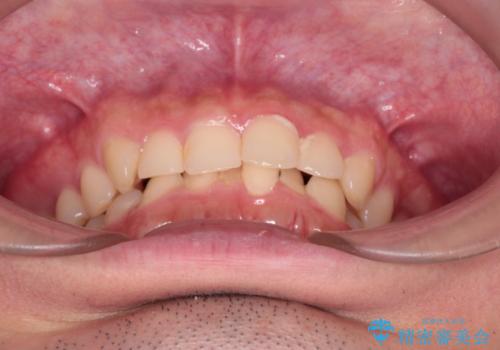

【インビザライン】前歯のガタガタと、前歯の噛み合わせが深いことを治したい。

- 前歯のガタガタと、前歯の噛み合わせが深いことを治したい。との主訴で来院されました。

シミュレーションを用いながら患者様と仕上がりについて相談しインビザラインにて治療を行いました。